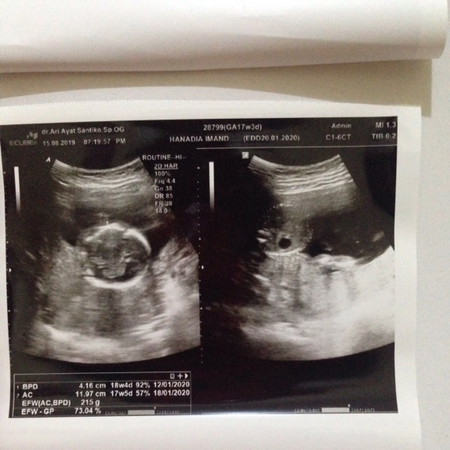

17w3d

Hi Bunda, sekedar sharing sore tadi saya usg uk 17w3d kehamilan anak pertama . Niat hati pengen usg 4D sama dokter disaranin besok aja kalo udh 6bulan ? kata dokter normal semua bun Puji Tuhan mulai dari jumlah jari terus tangan sama kaki jg lengkap . Cuma sayangnya saya kelupaan tanya mata, hidung, telinga, sama kuping ? saking fokus antara harus ngrekam usg nya (suami dikapal jd saya priksa sama nenek dr suami) sama dngerin deskripsi dokternya.. uk 17w3d udah dikasih tau jenis kelaminnya sama si dokter, itu kira2 akurat atau bisa berubah ya bun ? Uk 17w ada juga kah bunda2 yang udah ketauan jenis kelaminnya ?? Dan Puji Tuhan juga si baby lumayan aktif hihi kalo pas tiduran berasa banget ada yg gerak2 di perut ?